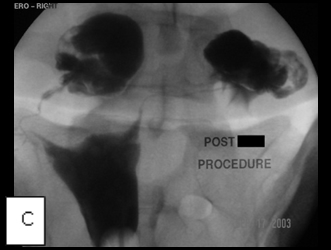

Images A, B, and C belong to a young woman who was referred to me for hysterosalpingography because of infertility and was shown at the examination to have bilateral cornual occlusion of the fallopian tubes. Image A shows contrast opacifying her endometrial cavity (red arrow), but not the fallopian tubes due to bilateral cornual occlusions. In image B, I have reopened the right cornual occlusion, filling a large right hydrosalpinx with radiocontrast (red arrow), and have a guide wire in the left fallopian tube (blue arrow), which implies relief of the obstruction. Image C, the final image, shows that both cornual occlusions are relieved, but there are bilateral large hydrosalpinges because of fimbrial adhesions, proven by the absence of contrast spill into the peritoneal cavity.